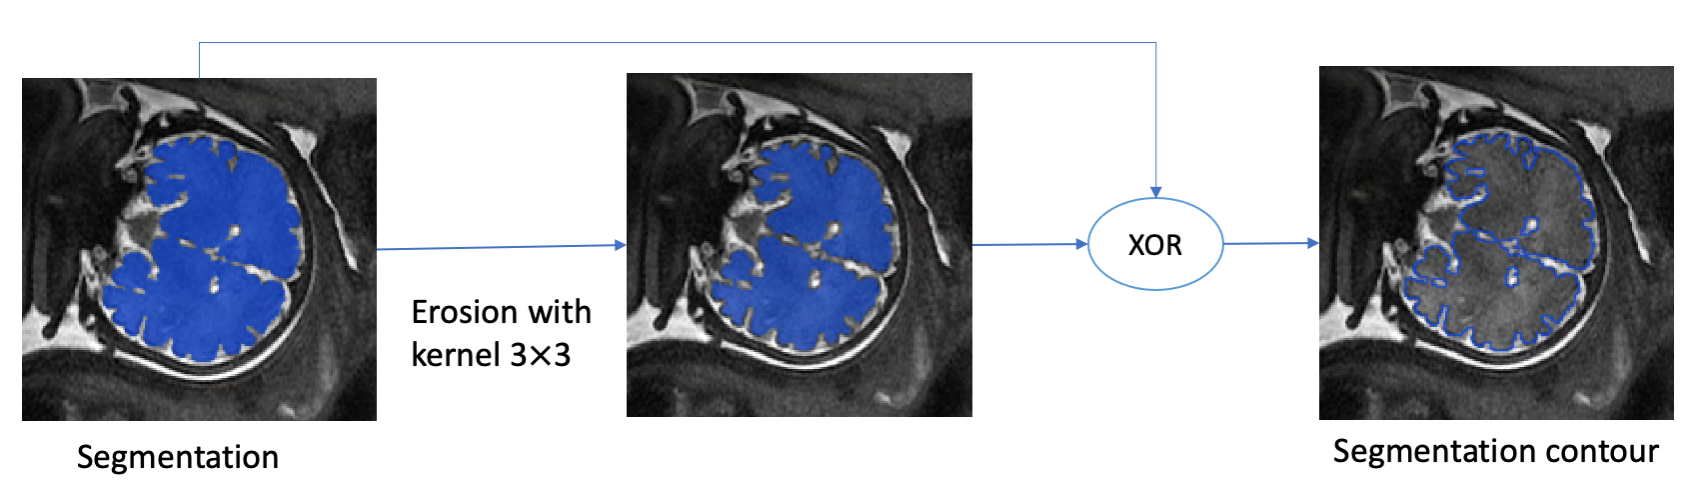

For the Contour Dice loss function calculation, we estimate the segmentation contours and from Eq. 1 with the erosion and XOR operators (Fig. 1). As a result, the computed contours have a width. We can now integrate over the contour voxels and formulate a loss function that is very similar to the original Contour Dice metric in Eq. 1.

3.1 Contours and Bands Extraction

The segmentation contour and the band around it are computed as follows. First, binary thresholding is applied to the network output with a predefined threshold . Then, the contours of both the network result and the ground truth segmentation are extracted using erosion and XOR operations (Fig. 1). Finally, the bands are extracted using erosion, dilation and XOR operations (Fig. 3).